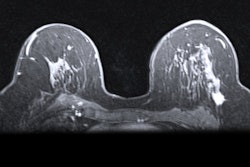

Scout is a wireless, radar-guided localization system used to assist breast surgeons in identifying biopsied tumors for removal during breast-conserving surgery. The study aims to enroll 500 patients to add to current literature supporting the use of the Scout system by improving efficiency in patient care between biopsy and surgery.

Merit said the study will include patients with high-risk breast lesions categorized as BI-RADS 4C or 5. Outcomes will be assessed from the initial placement of the Scout reflector during biopsy to its removal.